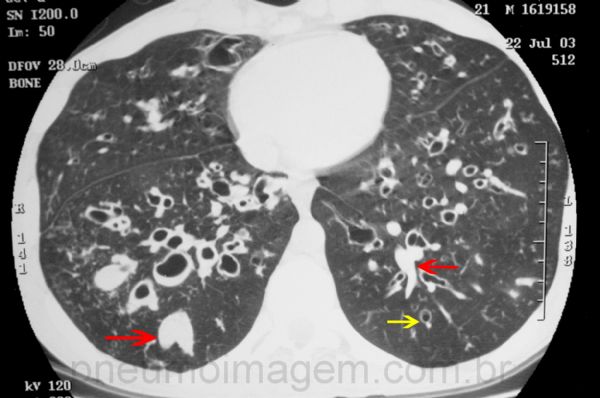

Neste paciente, as lesões alcançam também os lobos inferiores. Além das bronquiectasias centrais, pode-se observar o sinal do anel de pérola (muitas vezes chamado também de anel de sinete) - seta amarela -, e áreas de impacção mucóide (setas vermelhas), o conhecido sinal de dedo de luva.

In this patient, the lesions also reach the lower lobes. In addition to the central bronchiectasis, one can observe the sign of the pearl ring (often also called a signet ring) - yellow arrow -, and areas of mucoid impaction (red arrows), the well-known glove finger sign.